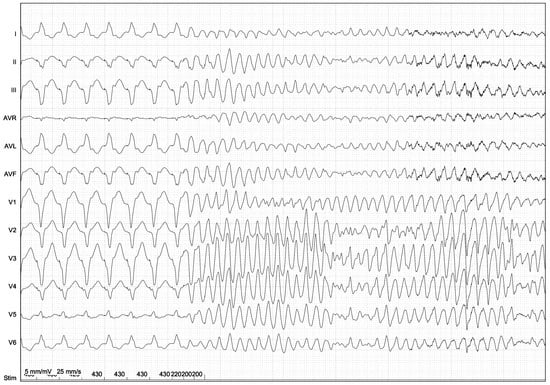

Figure 2.

Induction of ventricular fibrillation by programmed ventricular stimulation (PVS) in a patient with HCM. A basic drive train cycle length of 430 ms is followed by three extra stimuli with short coupling intervals (220, 200, and 200 ms) applied in the right ventricle. The prognostic significance of polymorphic VT and VF induced with PVS in HCM is unknown. Aggressive stimulation protocols may lack specificity when identifying true arrhythmic risk.